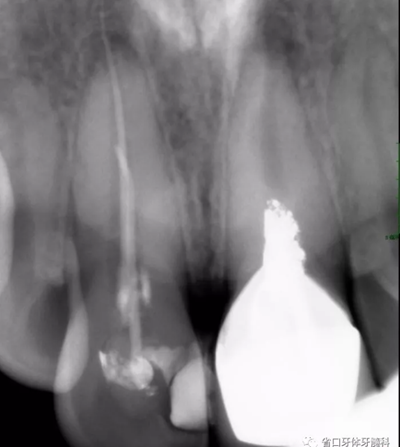

X線檢查:11冠部近中鄰面見(jiàn)高密度充填影像,邊緣有低密度線形暗影,根管內(nèi)見(jiàn)高密度稀疏影像,根管內(nèi)充填物與根管壁不密合,超出根尖孔約4-5mm,根尖周見(jiàn)低密度暗影;21根管上段修復(fù)體高密度影像,中下段根管空虛,根尖周見(jiàn)低密度暗影。圖3

圖3 治療前X線片